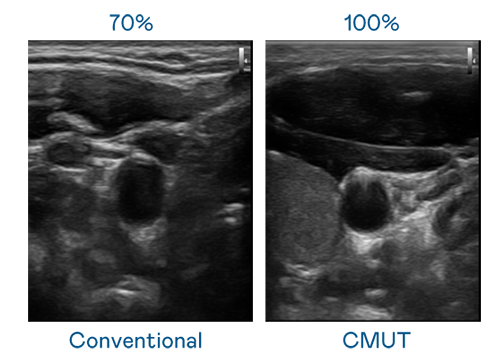

CMUT 技術是一種用電容式微機電元件來產生超音波訊號的技術。與傳統 PZT 壓電式技術相比,CMUT 頻寬增加 30%,更寬頻的超音波訊號讓影像解析度大幅提升,是實現高影像品質醫療超音波掃描、促進精準醫療發展的關鍵技術。

大頻寬帶來超清晰影像

超音波影像的解析度高低,首先取決於探頭能發出的訊號頻寬。金年会 CMUT 可提供高清晰的超音波訊號,提供高頻寬、高靈敏度、影像紋理細節更高的超音波影像,協助醫護人員縮短影像判讀時間及利用精準的醫療影像進行診斷。